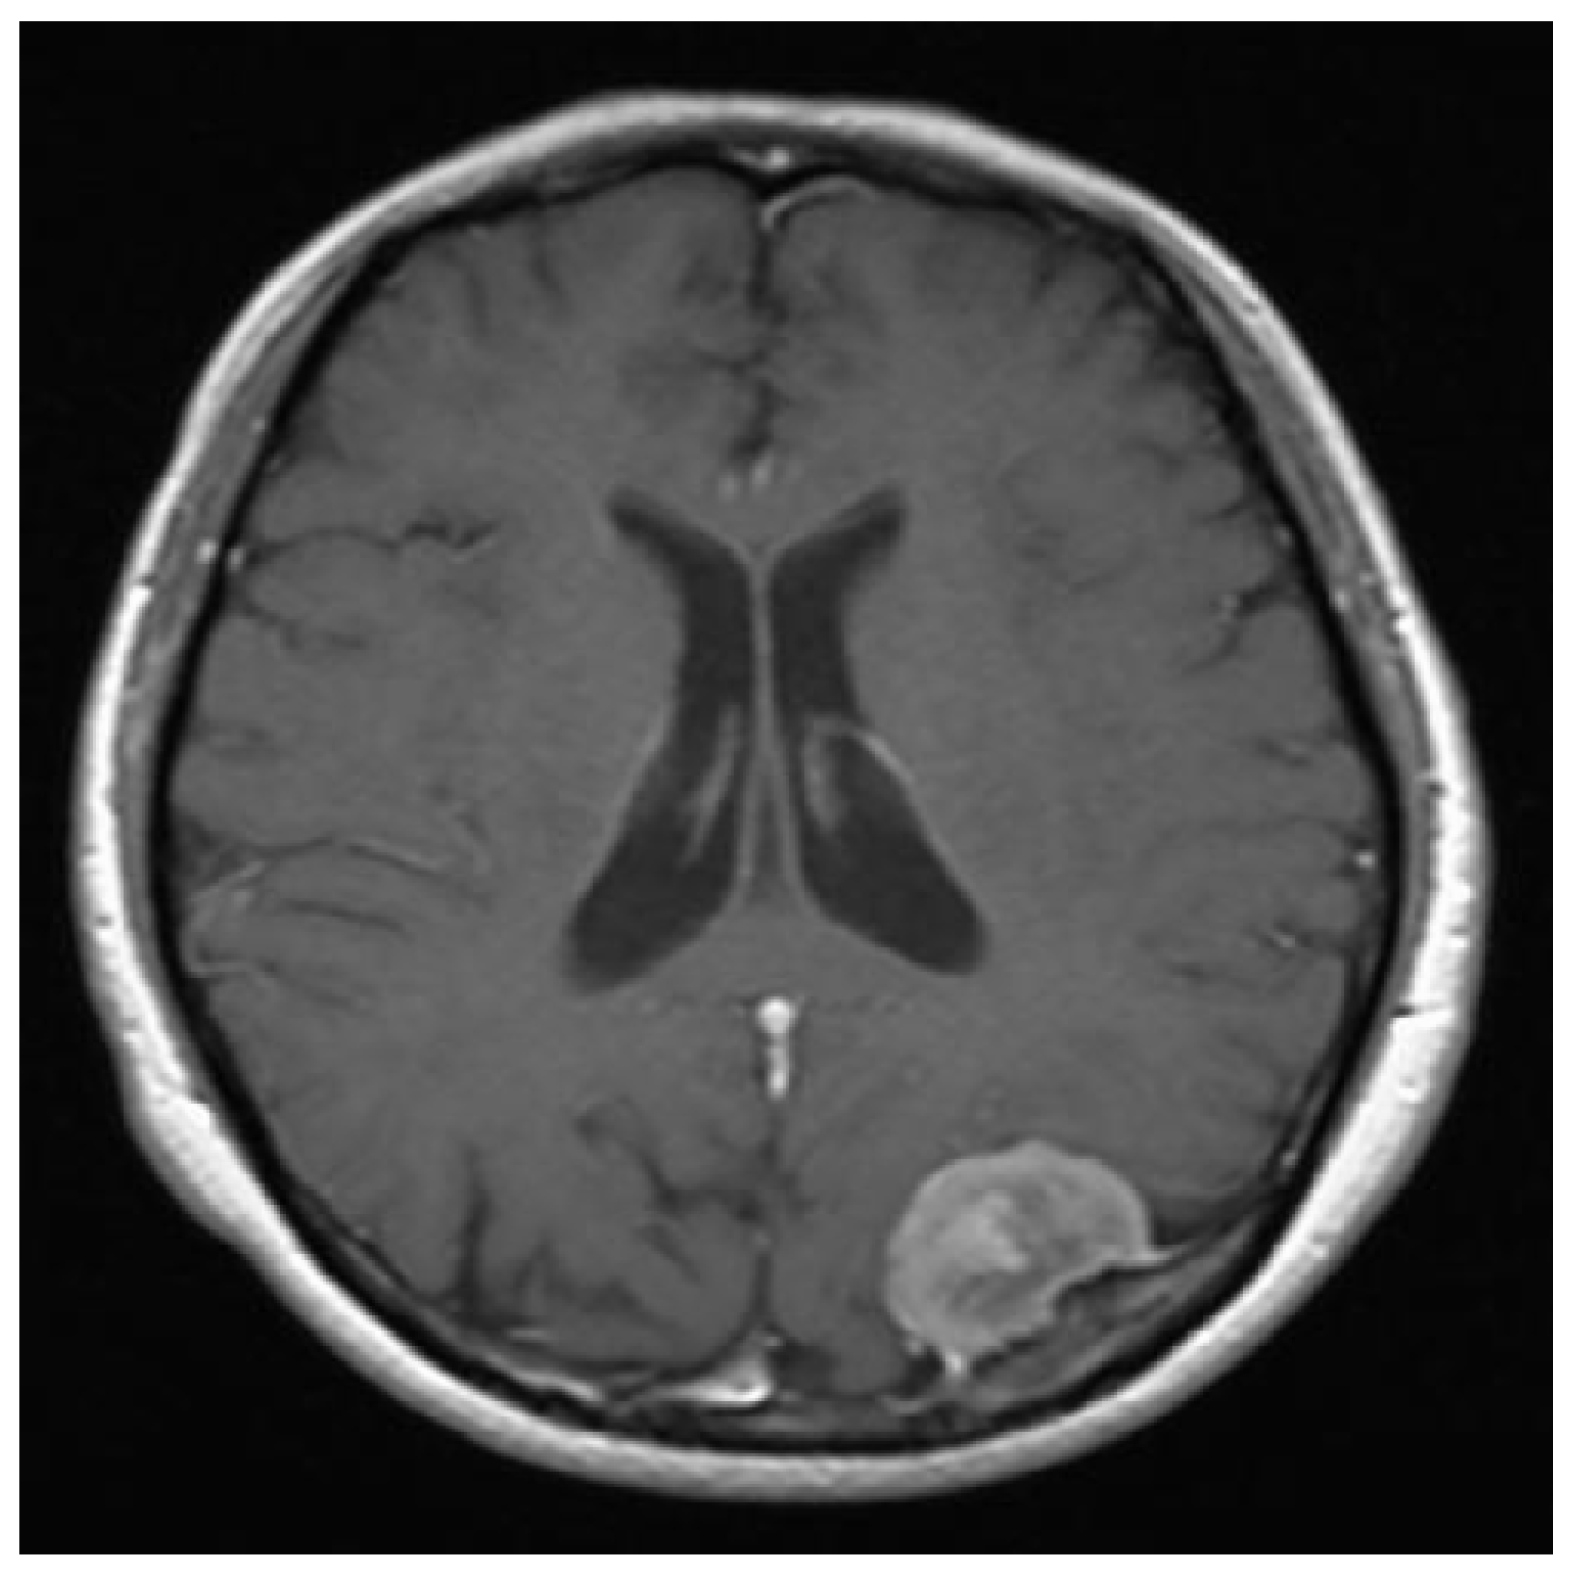

Figure 12.

The original clean image.

Figure 13.

The speckle noisy image with .

Figure 14.

The corresponding image segmentations. Left: Processed image by using our design. Right: Processed image by invoking the reference method.

Moreover, and by accepting the fact that there is no still a satisfactory performance measure index for a image segmentation process [13]. So far, we utilize the subjective evaluation criterion [13]. However, it is important to note that even when this criterion is widely used, an untrained subjective evaluation may result in a mistake conclusion [13]. Then, by suing the subjective evaluation measure to our processed noisy images, our technique, and according to our numerical experiments, presents an acceptable performance. On the other hand, the Jaccard similarity coefficient has also been extensively used for the performance evaluation of image segmentation methods. Recall that the Dice similarity coefficient is related to the Jaccard one. Essentially, the Jaccard coefficient, also known as the Tanimoto coefficient, measures the overlapping of two given sets, or two images in logical format, where a value of zero indicates no overlapping, and a value of one indicates a perfect agreement. Hence, if two segmentation processes are going to be compared, the one with the bigger Jaccard coefficient (or closer to one) value will have the better performance. Therefore, we proceed as follows in order to validate our performance segmentation algorithm by employing this Jaccard similarity coefficient in comparison to the reference method. Given the original image shown in Figure 12, we add the speckle noise to it. See Figure 13. Then, by utilizing this noisy image, the processed segmentation results are depicted in Figure 14. Then we transform the clean image into a binary image (logical format) by invoking the command im2bw of Matlad with a thresholding level of . We called it Image A. After transforming the colored images shown in Figure 14 into gray-scale images, we also transform them to their binary formats by employing the same previous command at the same thresholding level too. We call them Image B and Image C, respectively. That is, Image B is the resultant binary image of our processed image, and the other one coming from the corresponding reference method. Now, we are interested in comparing the similarity between Image A and Image B with respect to the similarity between the Image A and the Image C by invoking the Jaccard method. By doing it, we obtain and , respectively. Hence, our approach has a better performance.